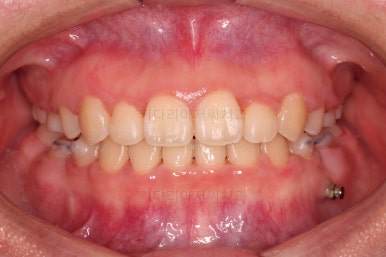

초진 때의 입안 모습입니다.

원래 다니던 치과에서 1년여 교정치료를 진행하신 상태였는데요.

몇 가지 이상한 점이 보이죠?

한 쪽만 발치가 되어있다.

아랫니에 유치가 2개가 그대로 남아있다.(화살표)

몇몇 이아에는 장치가 부착되어 있지 않다.

이원교정을 하신지 총 30개월 만에 남아있던 유치 자리가 잘 다물어졌고요.

이 뽑은 자리도 잘 메워졌고, 앞니도 가지런해졌어요.

위아래 치아 갯수도 동일하게 교합도 잘 맞췄고요.

예상보다 빠른 기간 안에 매우 만족스러운 치료였어요.

부산재교정 전후사진을 비교해 볼게요.

치열의 모습이 참 좋아졌고, 입매도 본인이 원하는 수준까지 좋아졌어요.